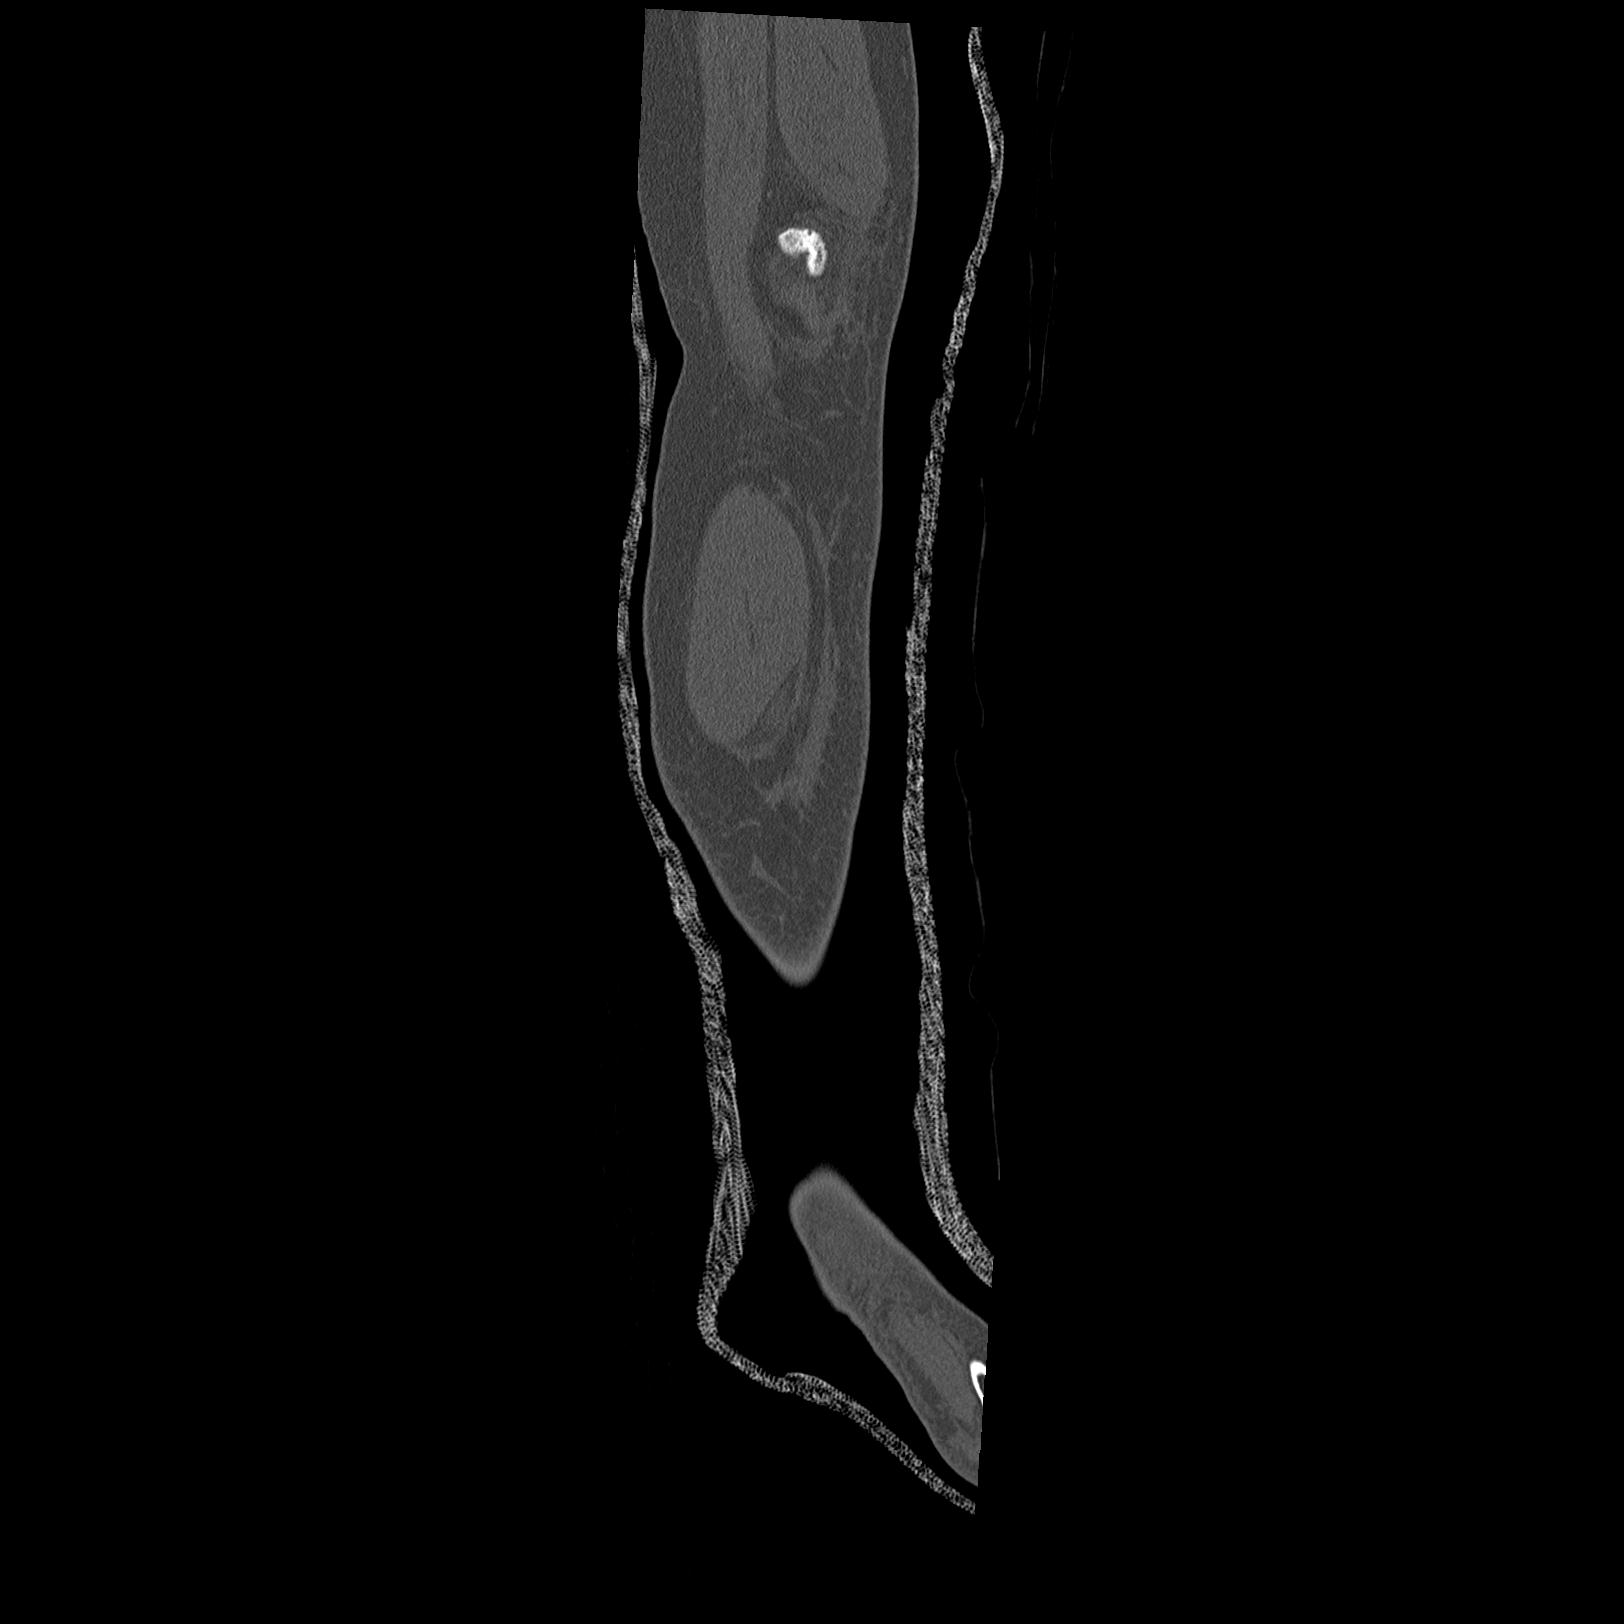

102803 1/12(キウスなし) 1/27 左下腿 4R 30歳女性 左脛骨軸内釘

110211 1/6 1/8 左前腕 4R 15歳男性 橈骨骨幹部骨折